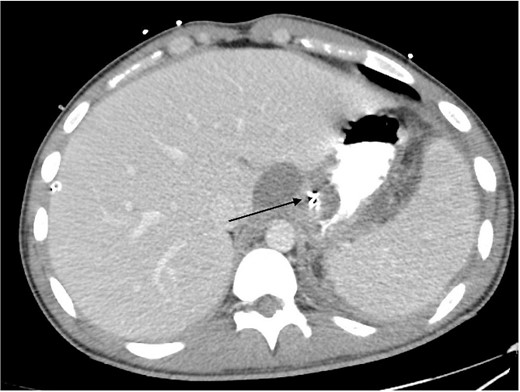

2L of pus was evacuated during laparoscopy, and it was converted to open due to limited views. At this stage, there was no obvious perforation. The entire colon was inspected, following splenic flexure and caecal mobilization. On inspection of the stomach, the wrap was intact with an unremarkable leak test. The decision was made to proceed with gastroscopy, whereby a 3 mm pinhole defect was seen at the GOJ at the 9 o’clock position, as shown in Fig. 2. Three haemostatic Cook Medical Instinct clips were placed, from distal to proximal, ensuring there was stable apposition of the perforated mucosa prior to deploying, as demonstrated in Fig. 3. Following this, the NGT was re-inserted under vision. The midline laparotomy was partially closed and Abthera dressing placed. The patient was taken to ICU intubated, with definitive closure performed 48 h later.

Gastroscopic image demonstrating the pinhole defect of the GOJ at the 9 o’clock position (arrow).